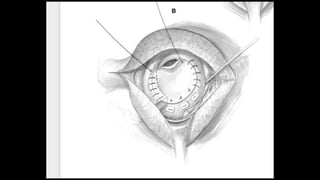

Figure 1 The chest is entered through a median sternotomy and the thymus gland is

removed. The pericardium is

opened and a portion is harvested and placed in glutaraldehyde for later use.

Examination of the external cardiac

anatomy shows the main pulmonary artery to be slightly enlarged and the right and

left pulmonary arteries to be quite

dilated, equal to or larger in size than the aorta. The segmental branches of these

vessels are small. For larger patients

we utilize aorto-bicaval cannulation and continuous cardiopulmonary bypass. For

smaller patients, especially those

with small superior venae cavae, we place aortic and right atrial cannulae. The

patient is then cooled to 18°C. During

cooling, the branch pulmonary arteries are mobilized out to the hilar branches. The

aorta is then cross-clamped and 30